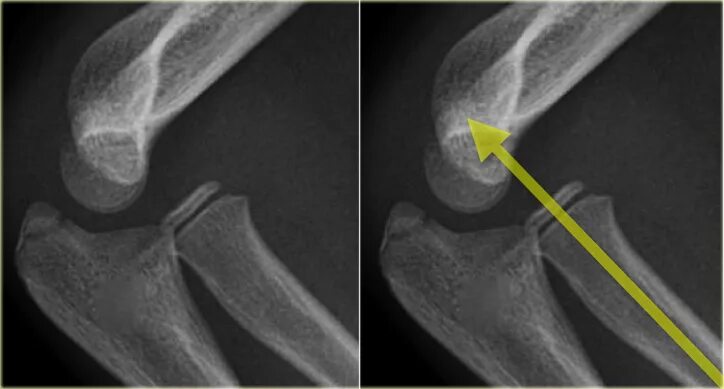

Подвывих локтевого сустава у ребенка